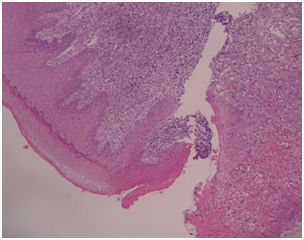

Macroscopic features: Received one bit of soft tissue, measuring about 2.8×2.8×0.9cms, reddish brown in colour, irregular in shape, lobulated in contour, firm in consistency (Figure 2). Tissue is grossed into A and B. A was taken for routine processing, B is retained.

Figure 2 Histopathological picture showing.

Histopathological impression

Section shows parakeratinised stratified squamous epithelium of inconsistent thickness underlying connective tissue comprising of numerous endothelial cells, budding capillaries. There are few bundles of collagen fibers along with fibroblasts. There is also presence of moderate inflammatory cell infiltration. Histopathological features are indicative of pyogenic granuloma (Figure 3). Based on the histological features diagnosis was confirmed as a pyogenic granuloma.